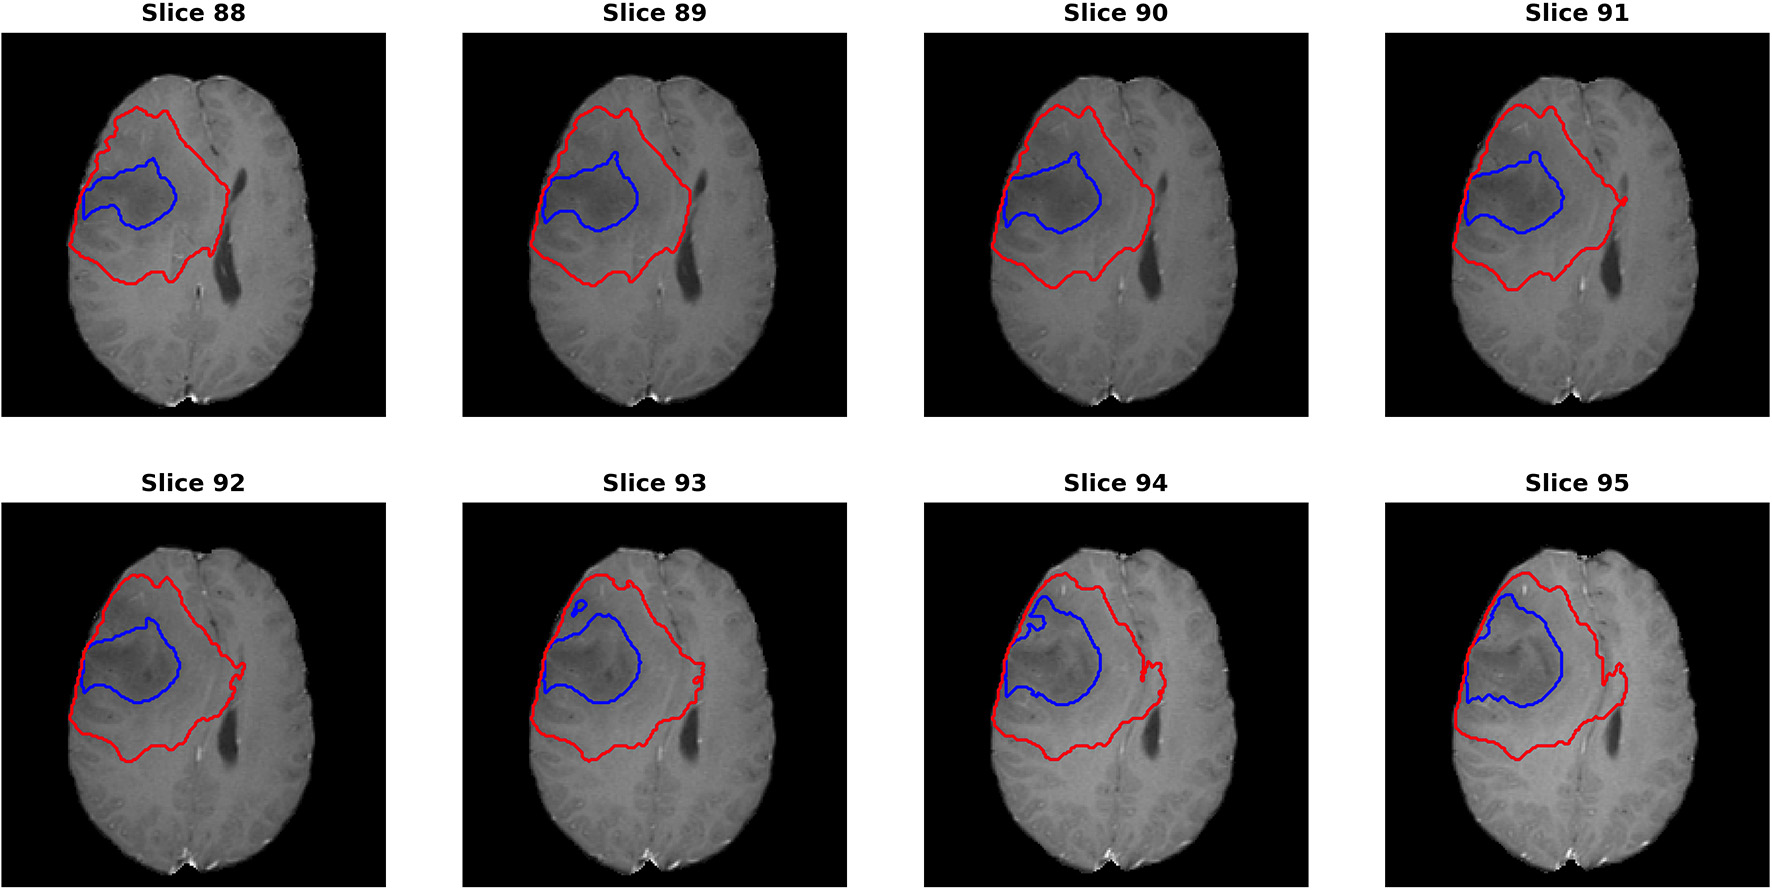

For the segmentation results, as we can get the evaluation for each individual case, it is noted that the median metrics were significantly higher than the mean metrics. For example, the median Dice scores were 0.870, 0.926, and 0.911 for ET, WT, and TC in the final ensemble model. It makes sense in that the theoretical maximum Dice score is 1 and minimum Dice score is 0. However, we noted that in several cases, the Dice scores were as low as 0 for ET and TC, meaning that the model completely missed the corresponding regions. Figure 7 shows an example (“Brats18_TCIA10_195_1”) with 0 Dice score for ET with post-contrast T1. Red and blue show the contours for WT and edema, respectively. No ET is detected in this case. However, it is indeed very difficult to identify the enhanced regions as the contrast enhancement is weak. Most of the subjects had the WT Dice score larger than 0.9, indicating very high segmentation quality. However, one case had a much lower Dice of 0.63. A careful examination showed that this case predicted a very small tumor region and the contrast was visually weak. It shows that although in most cases the automatic segmentation yields very accurate result, in difficult cases with reduced contrast and/or small tumor region, the automatic result may be sub-optimal and manual expert examination and correction is still required.

FIGURE 7

www.frontiersin.org

Figure 7. One case (“Brats18_TCIA10_195_1”) from the validation dataset showing failed segmentation for ET region on post-contrast T1. Red and blue show the boundaries for whole tumor and edema, respectively. No enhanced region is detected. It is indeed very difficult to determine the exact enhanced areas in the images, even for human experts.